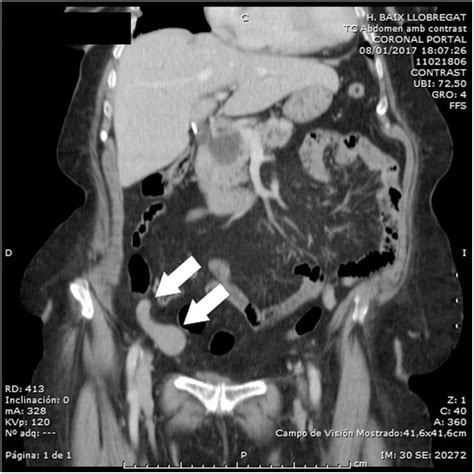

- Tomografía Computarizada (TC): Especialmente la TC con contraste, juega un papel crucial para el diagnóstico precoz. Puede revelar hipoatenuación del córtex renal bilateral, un fino halo de realce cortical subcapsular (el "cortical rim sign"), y ausencia de excreción del medio de contraste en la fase excretora, indicando isquemia cortical.